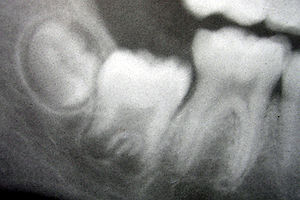

The developing tooth bud

One of the earliest steps in the formation of a tooth that can be seen microscopically is the distinction between the vestibular lamina and the dental lamina. The dental lamina connects the developing tooth bud to the epithelial layer of the mouth for a significant time.

Tooth development is commonly divided into the following stages: the bud stage, the cap, the bell, and finally maturation. The staging of tooth development is an attempt to categorize changes that take place along a continuum; frequently it is difficult to decide what stage should be assigned to a particular developing tooth. This determination is further complicated by the varying appearance of different histologic sections of the same developing tooth, which can appear to be different stages.